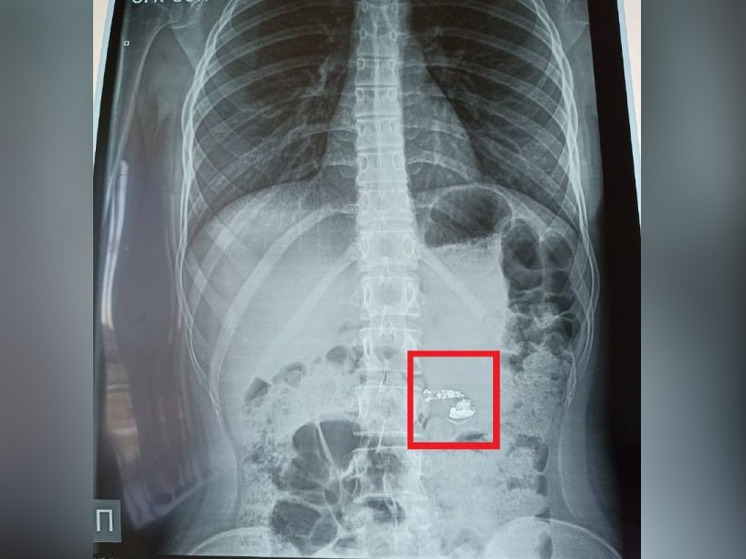

В столице Башкирии в больницу поступил 15-летняя девочка, которая во сне проглотила беспроводной наушник. Об этом в соцсетях рассказал министр здравоохранения республики Айрат Рахматуллин.

Школьница уснула с наушников в ухе и проснулась от боли в горле. Обнаружив пропажу наушника, девочка сразу же разбудила родителей, и они вызвали «неотложку». В больнице скорой медицинской помощи девушке сделали рентген и фиброгастроскопию, обследовав желудок, пищевод и 12-перстную кишку. Оказалось, что инородный предмет уже находился в кишечнике.

Подростка оставили под наблюдением в отделении детской хирургии. К счастью, операция не понадобилась, поскольку предмет вышел из организма естественным путем.